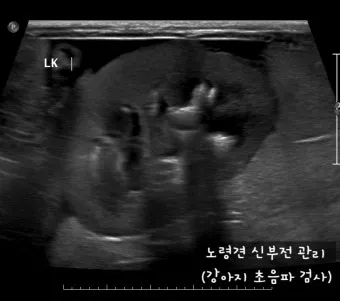

IRIS(International Renal Interest Society, 국제 신장 학회)에 따르면, 강아지 신부전은 1기부터 4기까지 총 4단계로 나뉘어 있습니다. 2기는 신장 기능이 매우 소폭 저하되어 큰 증상이 없는 단계예요.

장기적으로는 3개월마다 혈액검사를 받아보세요. 크레아티닌, BUN, 인 수치를 체크해서 화식이 효과가 있는지 확인하는 거예요. 수치가 안정적이면 지금 방식을 유지하시고, 악화되면 즉시 수의사와 상담하세요.

혈뇨나 단백뇨가 보인다면 더더욱 빨리 가세요. 신부전이 3기로 진행되고 있을 가능성이 높아요.